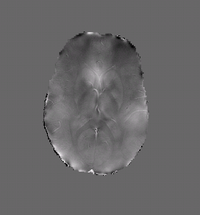

Susceptibility Map 1

Quantifying magnetic susceptibility in the brain from the phase of the MR signal provides a non-invasive means for measuring the accumulation of iron believed to occur with aging and neurodegenerative disease.

We describe a variational approach to susceptibility estimation that incorporates a tissue-air atlas to resolve ambiguity in the susceptibility estimates, while eliminating additional biasfields through application of the Laplacian.

Results show improved correlation with postmortem iron concentrations relative to competing methods.

• Algorithm: Improved background field correction, resulting in improved mean susceptibility values:

Thalamus ( -0.06 ppm )

Caudate (0.02 ppm)

Putamen (0.05 ppm)

Globus Pallidus (0.11 ppm)